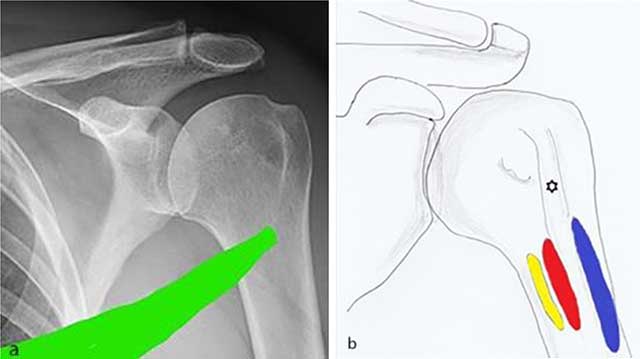

Figure 6

a) Spiral anatomical course of the teres major which may explain shearing forces leading to the periosteal stripping is demonstrated. b) Anatomical drawing showing the close anatomical relationship of the insertion of the teres major (yellow), latissimus dorsi (red) and pectoralis major (blue) tendon.

The spiral course of the teres major generates rotational forces (Figure 6) [3]. As a consequence, trauma may result in a broad-based periosteal stripping lesion, which will curl up and progressively calcify during the follow-up of the lesion. The mechanism is comparable with medial femoral epicondylar periosteal stripping in Pelligrini-Stieda or with periosteal stripping occurring in common adductor insertion avulsion of the thigh (thigh splint) [45]. Due to its close anatomical relationship with the tendinous insertion of the latissimus dorsi, an avulsion fracture of both tendons may co-exist (Figure 6) [6]. Teres major tears are predominantly seen on imaging at the distal musculotendinous junction (MTJ). Generally, MTJ lesions are divided in three grades. A grade 1 tear shows feathery edema around the MTJ. A partial disruption is categorized as grade 2 lesion whilst a complete disruption is a grade 3 lesion [7]. Imaging findings of a tear at the tendon bone insertion has – to the best of our knowledge – not been reported yet.